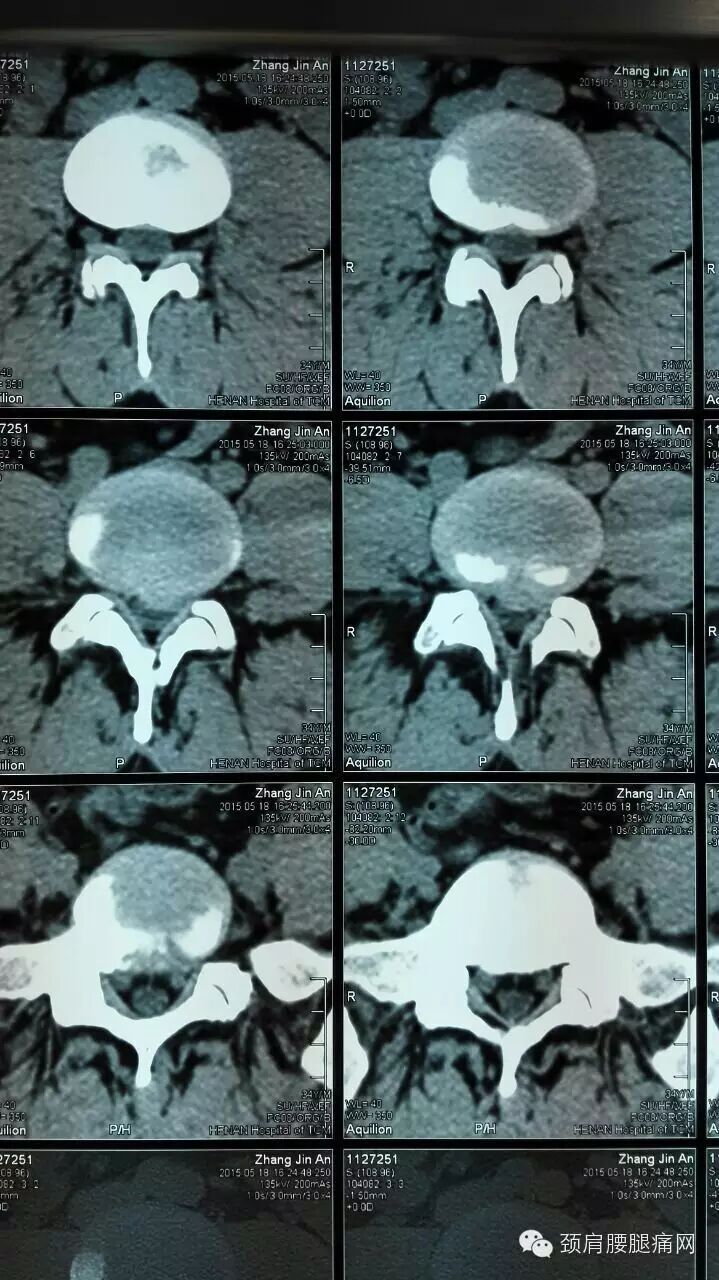

2015年5月18日下午,来了一位34岁的年轻患者,张某某,以腰痛伴右下肢后侧麻木2月为主诉来河南省中医院疼痛科就诊。

CT如下图所示:腰4、5椎间盘明显突出、侧隐窝狭窄。